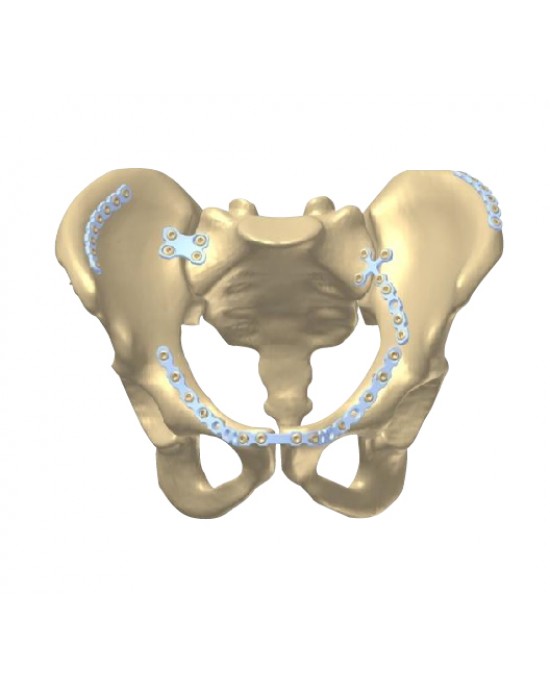

The complex anatomy of the pelvic ring and acetabulum involve complex surgical exposures and demands exact anatomical reduction to achieve positive functional results. Designed to treat a wide variety of challenging pelvic fractures, the MANTAROTM Pelvic Plating System contains a wide range of implants, reduction instruments, retractors and instruments for screw and plate fixation for the operative treatment of pelvic and acetabular fractures. Indication-specific plates are offered, as well as reconstruction-style plates to address a variety of fracture patterns that may occur.